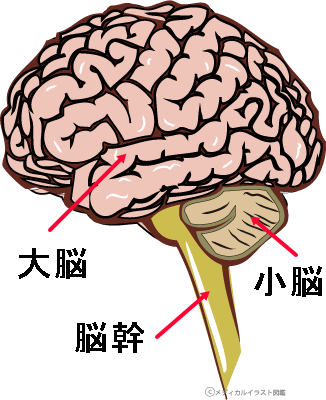

脳 脳幹 大脳 小脳 のしくみや働きがすぐわかる 高次脳機能障害の全て

脳の構造と役割 子供の脳の発達のための 脳育jp 子どもに健やかな成長と健全な発達を